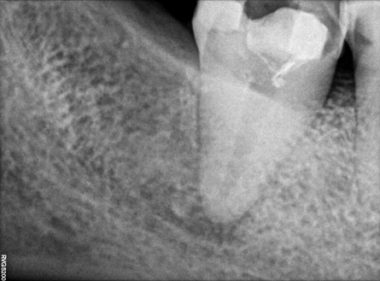

Patient Name: Asha Mane

Tooth Number: 47,48

Diagnosis: Radicular Cyst with 47,48

Treatment : endodontic treatment with 47, Extraction with 48.

File system used : TRUESHAPE 3D, Vortex Blue

Pre-operative

Obturation

After extraction with 48

Follow up after 3 months

Master cone after 1 month

Follow up after 6 months